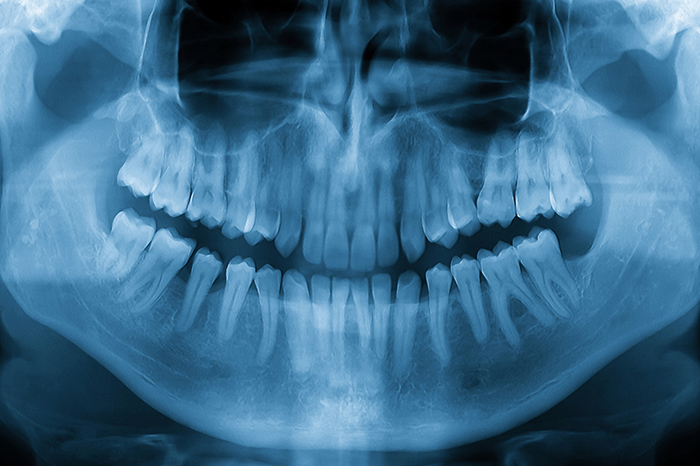

むし歯治療について

むし歯は放置すると、痛みや腫れだけでなく歯を失う原因にもつながります。当院では、できるだけ削らず、抜かずに治すことを大切にし、歯を守る治療を心がけています。銀座エリアで精密な診断と丁寧な処置を行い、むし歯の進行を抑える治療を追求。痛みに配慮した治療環境で、安心して通っていただける体制を整えています。

当院では「歯を守る治療」を第一に考え、健康な歯質を可能な限り残すよう努めています。マイクロスコープや拡大鏡を用いた精密な視野で、処置を実現。むし歯の進行度を見極め、削る量を抑えながら再発を防ぐ治療を行います。天然の歯を長く保ち、一生自分の歯で噛めるようサポートしています。